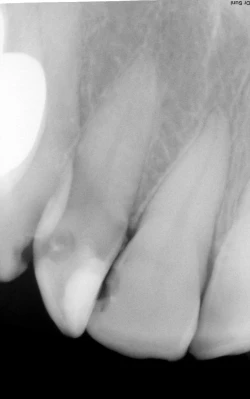

Bài viết này cũng thực sự hữu ích cho các bạn sinh viên mới ra trường đang tập tiếp xúc chẩn đoán các case đơn giản và hình thành tư duy điều trị. Dưới đây là một số hình ảnh thấu quang thông thường hay gây nhầm lẫn là sâu răng trên phim cánh cắn và cận chóp do yếu tố ngoài cấu trúc của răng: chụp phim và vật liệu phục hình, không xét tới yếu tố triệu chứng. Mọi chẩn đoán để đạt được chính xác cần kết hợp giữa triệu chứng lâm sàng và X-quang, thiếu một trong hai yếu tố sẽ dẫn tới những sai lầm trong điều trị.

Hình 1: Chu vi chân răng có những điểm lồi lõm nên khi hướng tia X-quang đi qua sẽ tạo hình ảnh thấu quang ở vị trí ranh giới thân – chân.

Hình 2: Các vùng thấu quang cổ răng trên nhiều răng cùng một góc độ chụp và cường độ tia. Chú ý vùng thấu quang ở vị trí nghi vấn dưới mối hàn xoang II Black (hình trái). Chẩn đoán phân biệt bằng triệu chứng và đánh giá độ tụt lợi.